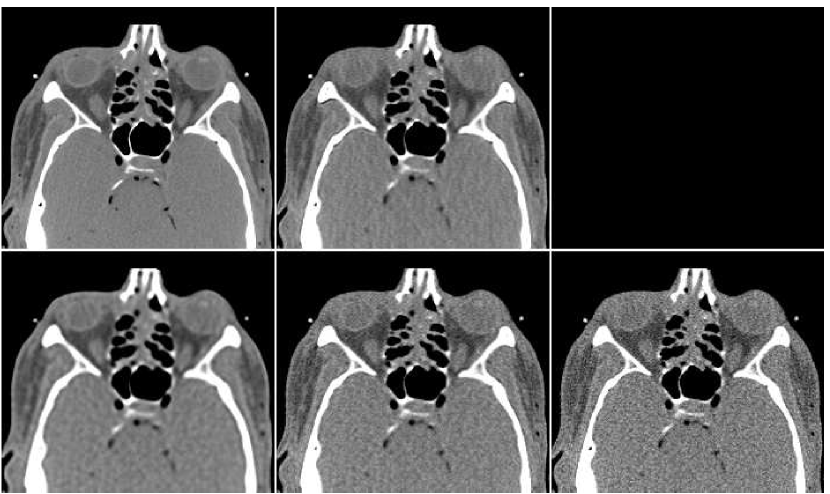

In Figure 10 we display the fusion result along with individual PWLS reconstructions, used in the fusion process. The lower part of the figure contains the absolute-valued error images. The fusion result has a higher visual quality than any of the three underlying images. Comparing to those images, the noise level in the fusion image is the lowest, and the tissue texture is closer to the original. The sharpness is the same as in the lower middle PWLS image. The SNR values (stated in the Figure) also point to the improvement in quality. The SSIM of the fusion image is , while the sequence of PWLS results have the SSIM values of (corresponding to the lower row of Figure 10, left to right). A reconstruction of an additional test image is displayed in Figure 11. The effect of the fusion observed here is similar to the one in the previous reconstruction. We conclude that the ANN-based fusion can contribute also to the iterative reconstruction, without requiring any additional iterations; the computational cost of the fusion, exercised after the reconstruction, is lower by an order of magnitude than that of the iterative process.

In order to test the robustness of the training results, we apply the ANN trained with the thigh sections, for a reconstruction of images of other body parts – sections of the head and the abdomen. Reconstruction results are presented in Figure 13 in the same order as in the previous comparison: middle image in the upper row is the result of fusion, which components are presented in the lower row. The head reconstruction is improved substantially by the fusion process, as visual observation shows. However, the SNR values (given in Table II) point to the favor of the PWLS image corresponding to iterations (lower middle image). The highest SSIM value does belong to the fusion result, though. In the case of the abdomen section, the fusion image is similar to the -iterations version but contains less noise; its quantitative measures are somewhat better than those of the individual PWLS images.